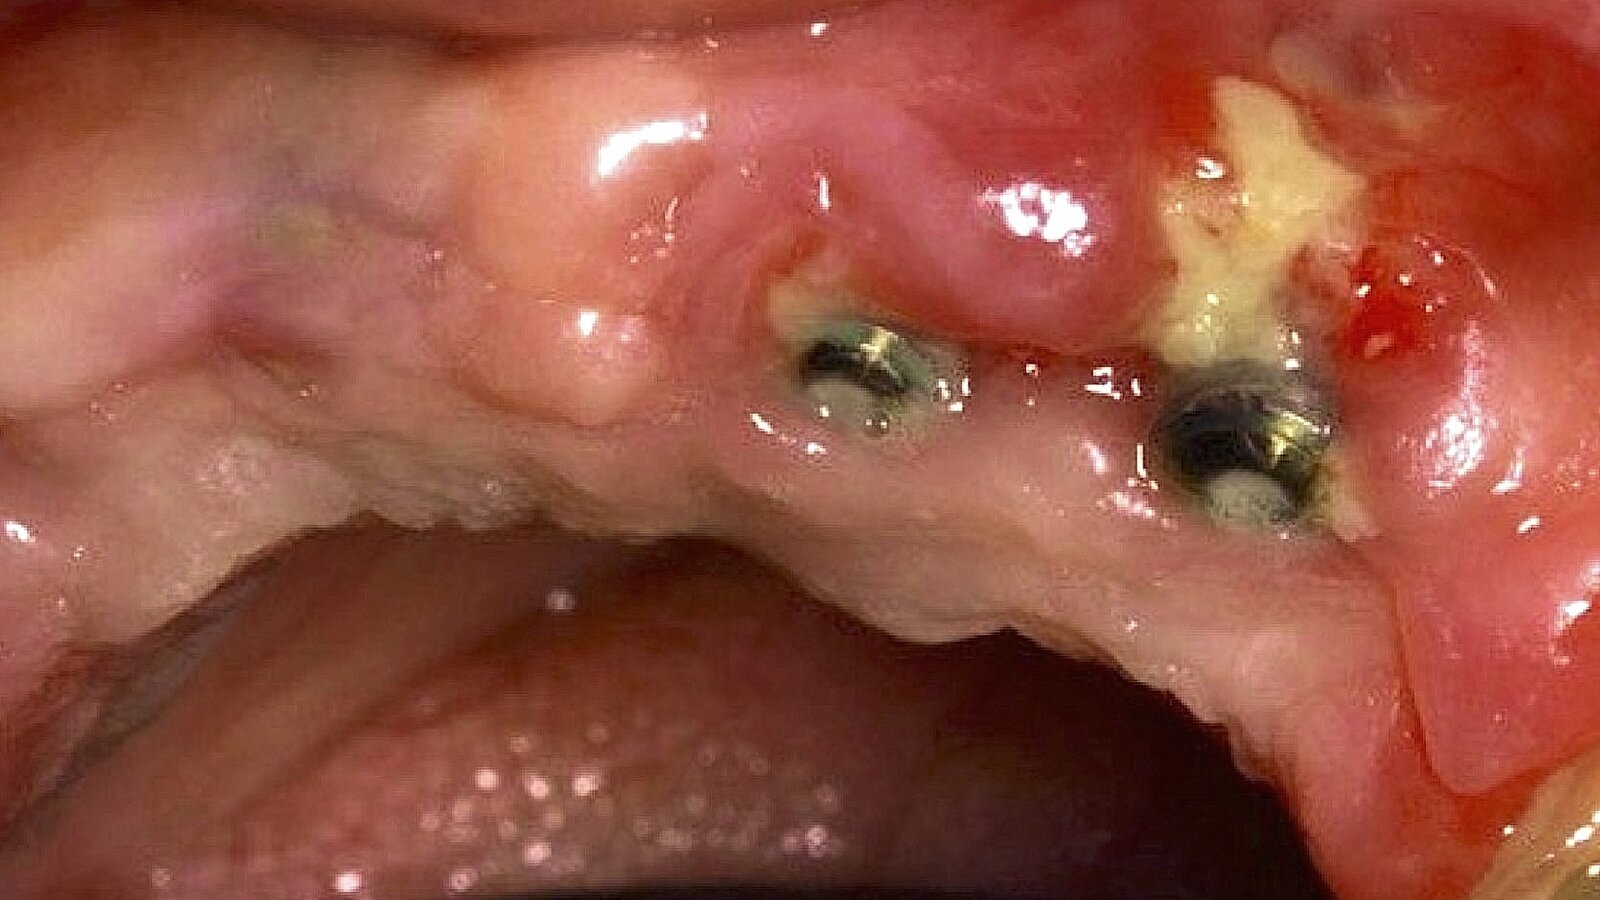

Figura 3. Osteonecrosis maxilar como consecuencia de un tratamiento con un antiangiogénico (anticuerpo monoclonal).

Existen otros mAbs que han sido reportados por MRONJ, dentro de los que se encuentran los siguientes: Bevacizumab[5] (antiangiogénico que actúa uniéndose al factor de crecimiento endotelial vascular VEGF), Nivolumab[6], Pembrolizumab5 y Ipilimumab[7] (inmunomoduladores utilizados en la terapia para varios tipos de cáncer que son inhibidores del punto de control inmunitario), Adalimumab[8] e Infliximab[9] (inhibidores del factor de necrosis tumoral alfa TNF-alfa, utilizados para tratar artritis reumatoide, psoriasis, enfermedad de Crohn, colitis ulcerosa).

Las intervenciones quirúrgicas orales, como extracciones dentales y la cirugía de implantes[10] en pacientes tratados con anticuerpos monoclonales incrementan el riesgo de osteonecrosis maxilar debido a la cicatrización deficiente y la alteración inmunológica. Además, los individuos con comorbilidades como diabetes mellitus, enfermedades autoinmunes o trastornos hematológicos tienen un riesgo elevado de desarrollar esta condición. Factores locales, como infecciones periapicales[11], periodontales[12] y perimplantarias[13], también pueden contribuir a la aparición de MRONJ.